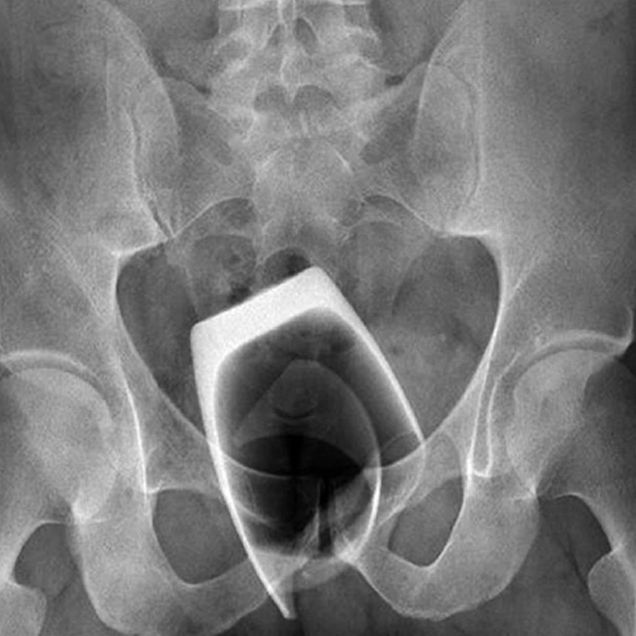

Potrivit surselor RefleqtMedia, un bărbat, în vârstă de aproximativ 48 de ani, s-a prezentat la UPU Cluj cu un borcan de 400 ml înfipt în… anus!

Nu se știe cum a reușit omul să-și înfigă ditamai borcanul în vintre și nici ce îndeletniciri a avut pentru a ajunge în această situație, dar cert este că doar intervenția RAPIDĂ și EFICIENTĂ a personalului medical de la UPU Cluj i-a salvat viața omului.

Dacă borcanul respectiv se spărgea, cioburile rezultate l-ar fi omorât pe om, provocându-i o hemoragie infernală!